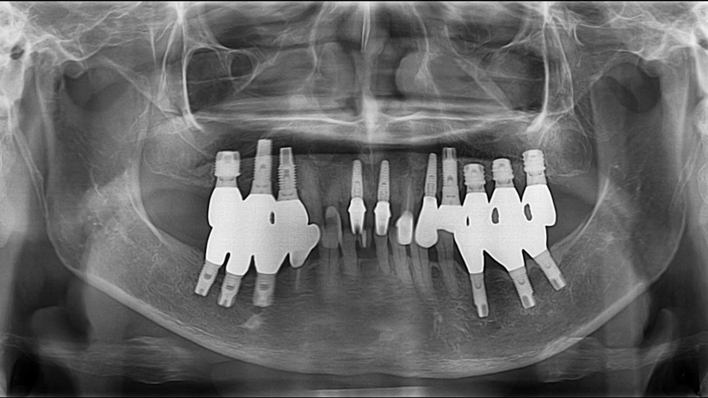

Clinical case: Extraction, immediate placement & loading using

R2GATE solution in aesthetic zone

- Courtesy of Dr. Jong-Cheol Kim, Korea-

Dr. Jong Cheol Kim, immediate loading, digital guided surgery, Digital ONE-DAY Implant, maxillary anterior, #21, guided surgery, immediate loading, AnyRidge, R2GATE, Mega ISQ, MEG Torq, R2GATE Full Surgical Kit

AnyRidge implant system, R2 Guide, R2GATE Full Surgical Kit, Mega ISQ